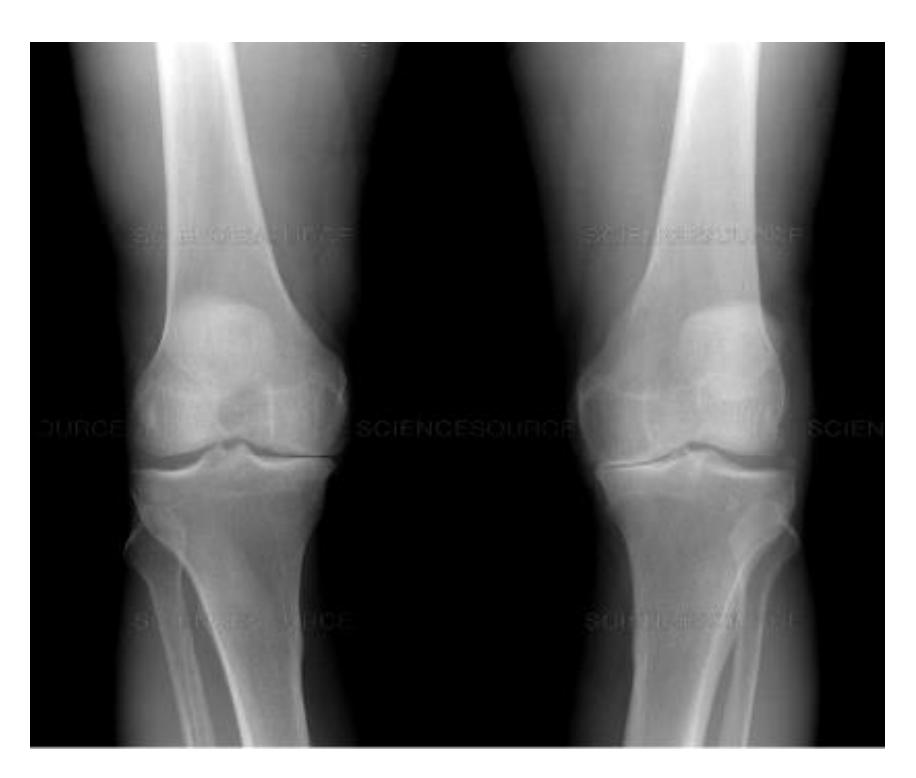

A 60-year-old overweight lady presented to clinic with chronic pain in both knees. A standing AP x-ray of both knees is shown.

Q1: Mention TWO findings on this X-ray

- Narrowing of the joint space

- Osteophytes

Q2: What is the diagnosis?

- Bilateral knee osteoarthritis

X-ray Interpretation and Management

AP & Lateral x-ray of the knee joint showing narrowing of joint space & sclerosis

Diagnosis?

- Knee Osteoarthritis

Management?

- Exercise & analgesics

- Intra-articular injection

- Knee arthroplasty (depends on the case)